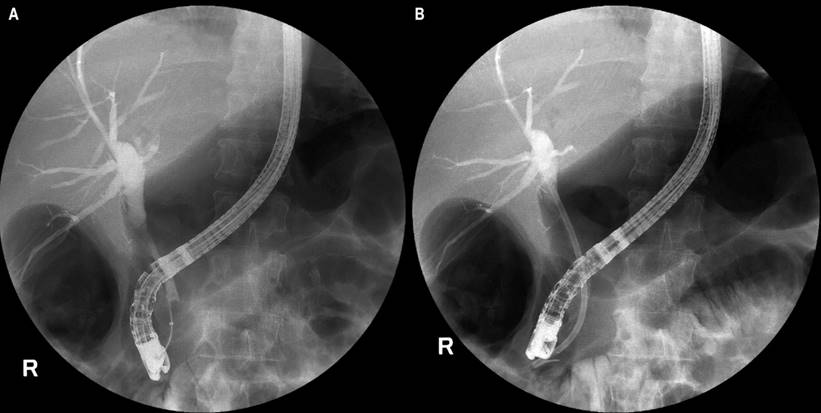

ERCP showed a narrowing of the common bile duct at the junction of the proximal third with the middle third, with dilatation proximal to the confluence of the hepatic ducts (Figure 3A). Papilotmy was performed with drainage of purulent bile fluid and extraction of stones with basket and balloon. It was decided to insert a 10 cm Teflon stent of 10 Fr with adequate drainage (Figure 3B).

Figure 3 ERCP. A. Dilation of the bile duct at the junction of the proximal third with the middle third of the common bile duct, proximal dilation to the confluence of the hepatic ducts. B. After insertion of 10 Fr Teflon stent of 10 cm. Image Archive of Hospital Universitario Hernando Moncaleano Perdomo in Neiva.